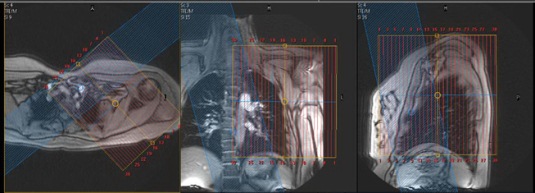

MR Scapula WO or W/WO Protocol

| SAG | T1 | TSE | 4mm | 1mm | None | 22cm | Perpendicular to scapula |

| SAG | T2 Fat Sat (TE=50-60) | TSE | 4mm | 1mm | SPAIR | 22cm | Perpendicular to scapula |

| COR | STIR | TSE | 4mm | 1mm | STIR | 25cm | Parallel to scapula |